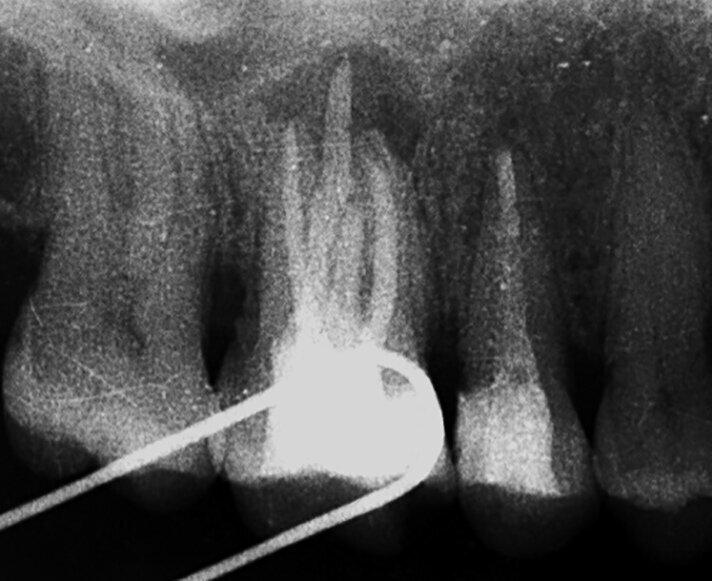

Les premières molaires (Fig. 7) sont étroitement associées au désir d’être reconnu dans la société comme dans la famille. L’atteinte des idéaux pour améliorer notre position dans la société est liée à la première molaire supérieure droite ainsi qu’à la première molaire inférieure droite, et ces dents reflètent notre vie professionnelle et notre réussite à cet égard. La patiente présentée à la figure 8 avait dû renoncer à sa passion professionnelle en raison de circonstances familiales qui l’avaient contrainte à déménager et demeurer chez elle. Après un traitement endodontique de la seconde prémolaire supérieure droite et de la première molaire supérieure droite (dents 15 et 16), elle a présenté une importante lésion périapicale de la dent 16 quelques années plus tard (Fig. 9). Elle n’avait probablement pas encore accepté sa nouvelle situation.